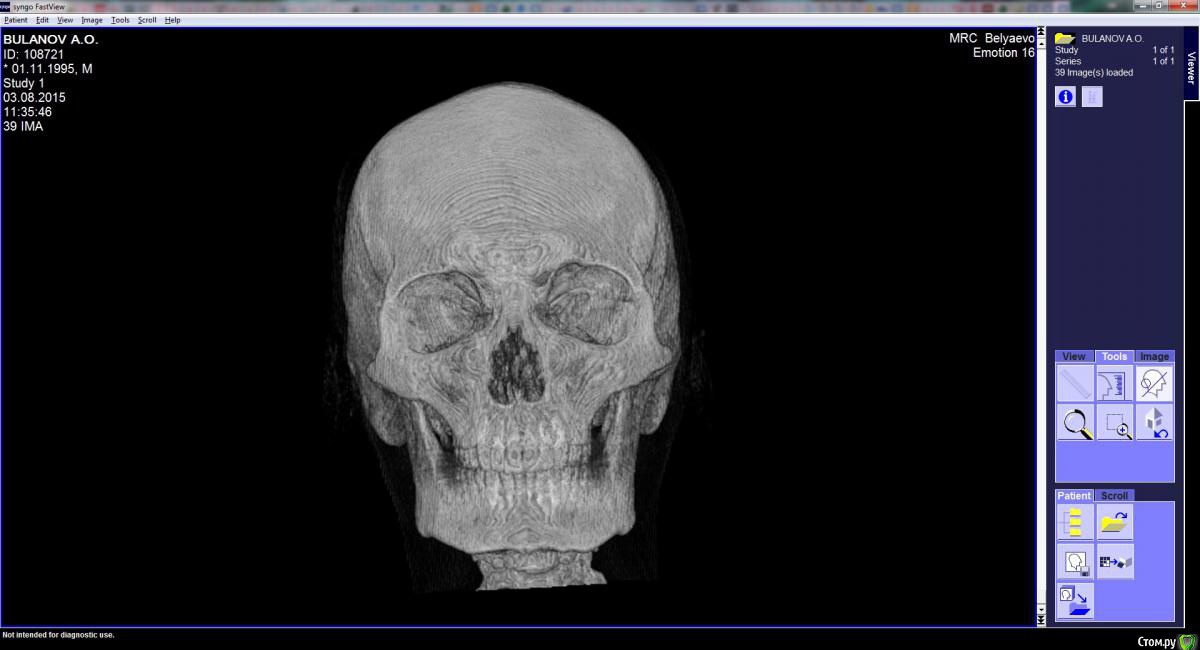

Arseny0111 Опубликовано 27 сентября, 2015 Поделиться Опубликовано 27 сентября, 2015 (изменено) Здравствуйте,в ходе драки получил удар,в верхнюю челюсть,сразу же не значительно сменился прикус и искривилась носовая перегородка.Есть ли на снимках отклонения от нормы?трещина?и т.д.Что с этим делать к кому обращаться?Из исследований дополнительно имеется МСКТ(3D)Спасибо. Изменено 27 сентября, 2015 пользователем Arseny0111 Ссылка на комментарий

Arseny0111 Опубликовано 1 октября, 2015 Автор Поделиться Опубликовано 1 октября, 2015 Здравствуйте,в ходе драки получил удар,в верхнюю челюсть,сразу же не значительно сменился прикус и искривилась носовая перегородка.Есть ли на снимках отклонения от нормы?трещина?и т.д.Что с этим делать к кому обращаться?Из исследований дополнительно имеется МСКТ(3D)Спасибо.Уважаемые доктора,помогите пожалуйста.Неужели нет компетентных специалистов в этой области? Ссылка на комментарий